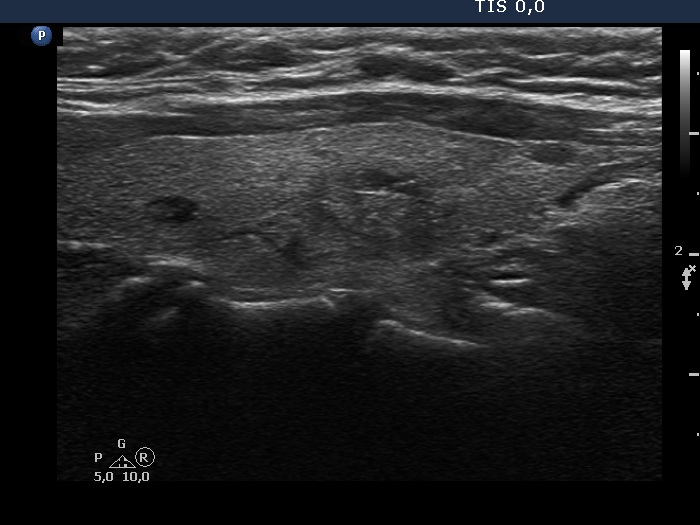

Parathyroid lesions - case 324 (ultrasonographic picture 6)

Right lobe, longitudinal scan